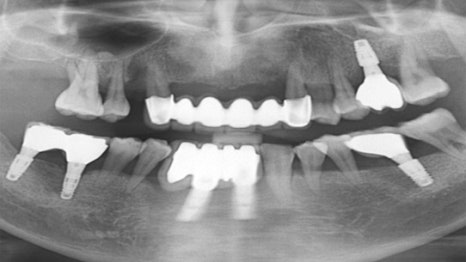

사례 2

크라운 치료를 통한 자연치아 보존

잇몸뼈가 약해 12개 임플란트를 권유받았던

환자분께 치주 치료를 진행한 결과,

전치부(앞니) 잇몸 상태가 개선되어 발치하지 않고

크라운 치료로 복원하였습니다.

어금니에는 6개만 식립하여 기능을 되살렸습니다.